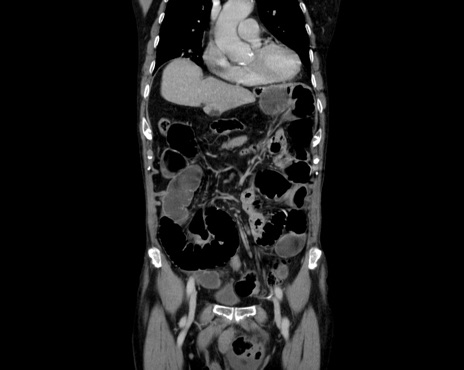

症例26(冠状断像)

【症例】80歳代男性

【主訴】嘔吐

【現病歴】昨晩2回嘔吐あり、今朝になっても嘔吐あり。来院。

【既往歴】胃潰瘍

【身体所見】意識清明、BT 37.6℃、BP 166/95mmHg、HR 100bpm、SpO2 97%、腹部:平坦・軟、腸蠕動音聴取良好、圧痛なし。

【データ】WBC 21900、CRP 1.4